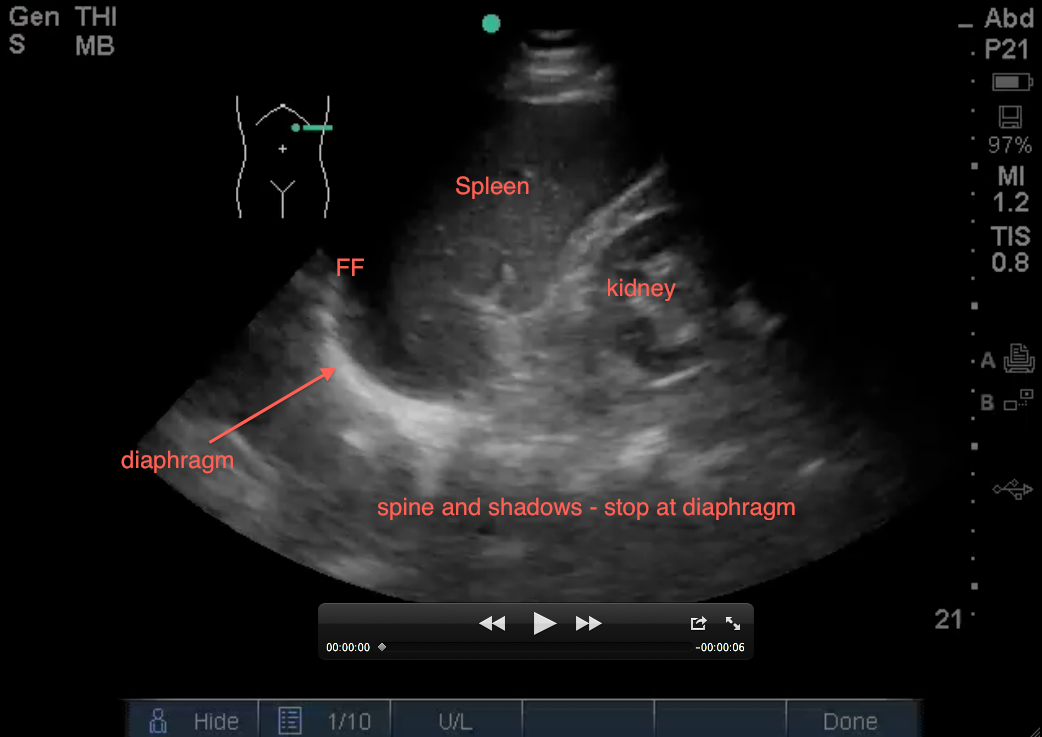

1. Evaluate above the diaphragm…. to evaluate for intrathoracic free fluid. This may involve having to increase your depth while you slowly fan your probe anterior to posterior (from 13cm to 16cm – you dont usually need to go 19cm unless it’s a huge spleen). The patient’s breathing will also help you as you will notice the bright white (echogenic) linear diaphragm which hugs the spleen will move (right and left) on your screen with every breath. Having the patient take a deep breath and holding it, will allow you better visualization if a rib shadow is in your way. A mirror image of the spleen may be seen above the diaphragm (a normal artifact that occurs when ultrasound passes through structures of varying densities and then through air (lung). However, in the LUQ, If no mirror image, it may not mean free fluid, especially if the stomach is in your view. If the area above the diaphragm is truly anechoic (black) without Stomach Sabotage – that’s fluid in the thoracic cavity! The spine sign will also help you evaluate for free intra-thoracic fluid, as the spine and it’s shadowing normally stops once it hits the diaphragm when visualizing on the screen from right to left (air is the enemy of ultrasound!). But if there is fluid in the thoracic cavity, you will see the spine continue to traverse past the diaphragm up into the thoracic area (fluid is the lover of ultrasound!).

2. Evaluate below the diaphragm… to evaluate for intraperitoneal fluid. This is where free intraperitoneal fluid will usually develop first in the left upper quadrant (LUQ) (different from the RUQ where the first area of free fluid is usually around the inferior pole of the kidney and right paracolic gutter). If you increased your depth for #1 above, you will need to adjust it back. You will be sabotaged by stomach when getting this view, so you may want to oblique your probe (indicator toward gurney as explained by Dr. Mike Stone) in plane with the ribs and angle your probe posteriorly (and thus away from the anterior stomach). Black fluid below the diaphragm between it and the spleen is abnormal as seen below: